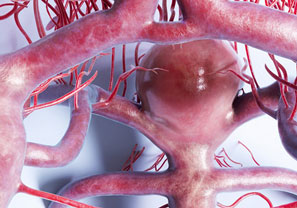

We believe in staying at the forefront of medical advancements. Our facility is equipped with the latest imaging equipment, ensuring accurate diagnoses and precise treatment planning. From angiography to fluoroscopy, we leverage cutting-edge technology to optimize patient outcomes.

Malformed connections between arteries and veins are referred to as aortovenous malformations (AVMs). In the lungs, larger arteries deliver blood to smaller arteries...